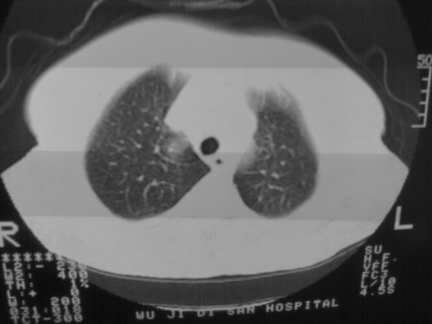

标题: CT13142:女 80 胸闷、气短、1w [打印本页]

标题: CT13142:女 80 胸闷、气短、1w

右肺炎性变

气管,支气管软骨钙化。

右肺感染;双侧胸腔少量积液,心影增大,可能与心功不全有关;胸内甲状腺肿。

胸内甲状腺肿;右肺感染;双侧胸腔少量积液。

胸内甲状腺肿;右肺中叶感染;双侧胸腔少量积液;心影增大,考虑有心功能不全。